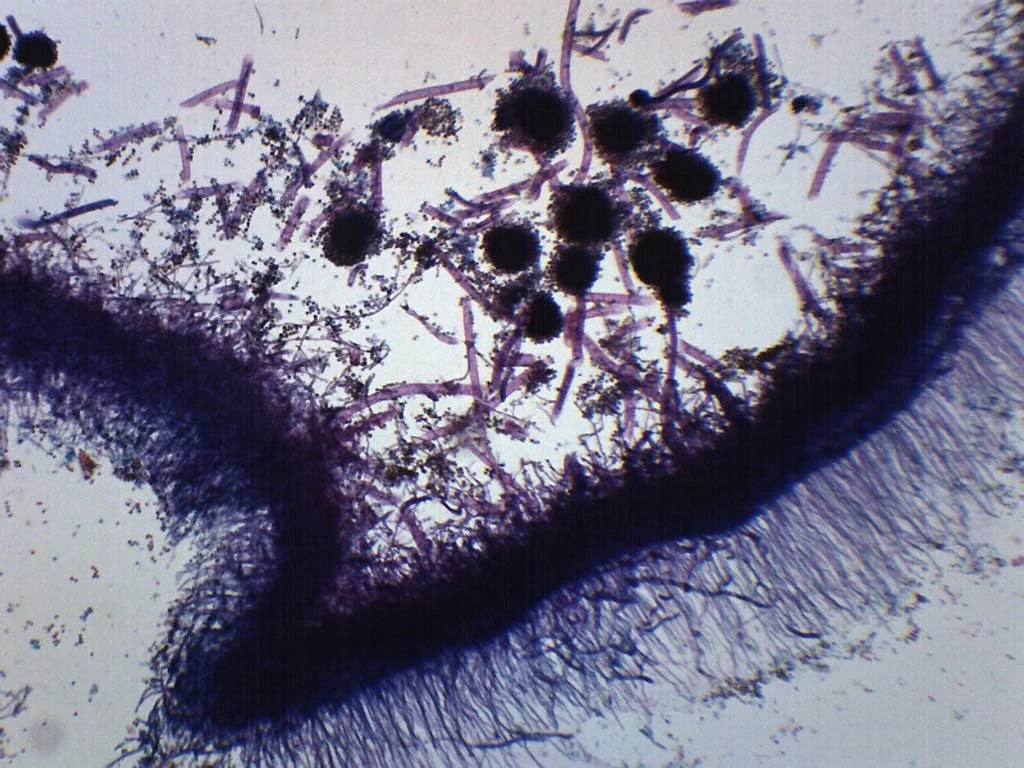

تجهیزات آزمایشگاهی شامل ابزارهایی متنوع با کاربری های بسیار خاص هستند. از تجهیزات پایه ای مانند بیکر، ارلن، پیپت و میکروپیپت گرفته تا دستگاه های پیشرفته ای مانند اسپکتروفتومتر، سانتریفیوژ، انکوباتور، هات پلیت و آون. این تجهیزات از جنس های مقاومی نظیر شیشه بوروسیلیکات، فولاد ضد زنگ یا پلاستیک های خاص ساخته می شوند تا در برابر مواد شیمیایی و دمای بالا مقاوم باشند. ابعاد، ظرفیت، درجه دقت، سرعت عملکرد و مصرف انرژی از ویژگی های مهم فنی این ابزارها به شمار می رود. برخی مدل های تجهیزات آزمایشگاهی دارای صفحه دیجیتال و سیستم های هوشمند کالیبراسیون هستند تا دقت اندازه گیری ها را به حداکثر برسانند.

بازار این تجهیزات مدل های متنوعی را برای نیازهای مختلف ارائه می دهد. برای نمونه، سانتریفیوژها در مدل های میکرو، بالینی و تحقیقاتی عرضه می شوند؛ یا انکوباتورها ممکن است دارای کنترل CO2 یا رطوبت باشند. اسپکتروفتومترها نیز در انواع UV-VIS، نیر قرمز یا دوبل بیم موجودند. علاوه بر این، تجهیزات مصرفی مانند لوله آزمایش، نوک میکروپیپت، پتری دیش، و دستکش آزمایشگاهی در اندازه ها و کیفیت های مختلف قابل تهیه هستند. شناخت این تنوع ها به کاربر کمک می کند تا بهترین انتخاب را بر اساس نوع پروژه و بودجه خود انجام دهد.